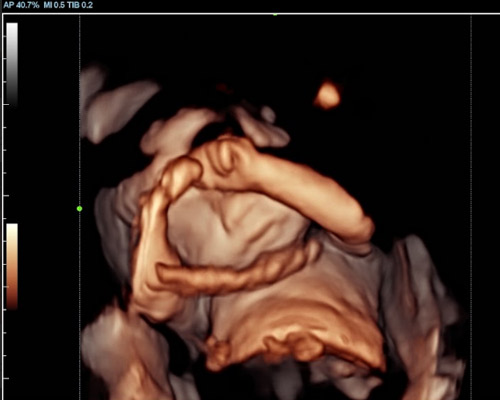

A 3D/4D bonding scan combined with a heartbeat bear near Wakefield offers a unique way to experience both visual and emotional connection before birth.

A 3D scan captures detailed still images of your baby’s face and body, while a 4D baby scan Wakefield allows you to see those images in motion. You may notice movements such as stretching, turning, or subtle expressions, making the experience feel more real.

With a 4D baby ultrasound Wakefield, this technology allows you to see your baby with greater clarity and depth. The result is softer, more lifelike visuals that can feel closer to a photograph than a traditional scan.

Our Scans